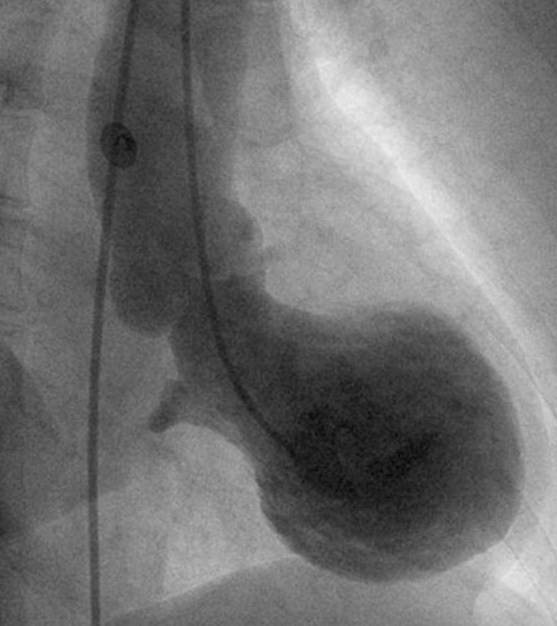

Leonarda Galiuto, prima autrice della ricerca, spiega così il lavoro svolto: “Ci siamo concentrati sulla regione apicale del cuore, perché’ e’ li’ che e’ ubicata la disfunzione,

tanto che il cuore assume la caratteristica forma a palloncino o, come hanno osservato i giapponesi, a forma di cesta per raccogliere i polipi, il Tako-Tsubo e’ appunto il nome di questa cesta

in giapponese”.

Conclude allora Crea: “Nel paziente normalmente non rimangono danni perché’ la riduzione nell’apporto di sangue e’ si’ abbastanza grave da non fornire energia sufficiente al cuore per

contrarsi, e di qui la forma ‘a palloncino’, ma non cosi’ grave da determinare la morte delle cellule cardiache come invece avviene in un infarto”.